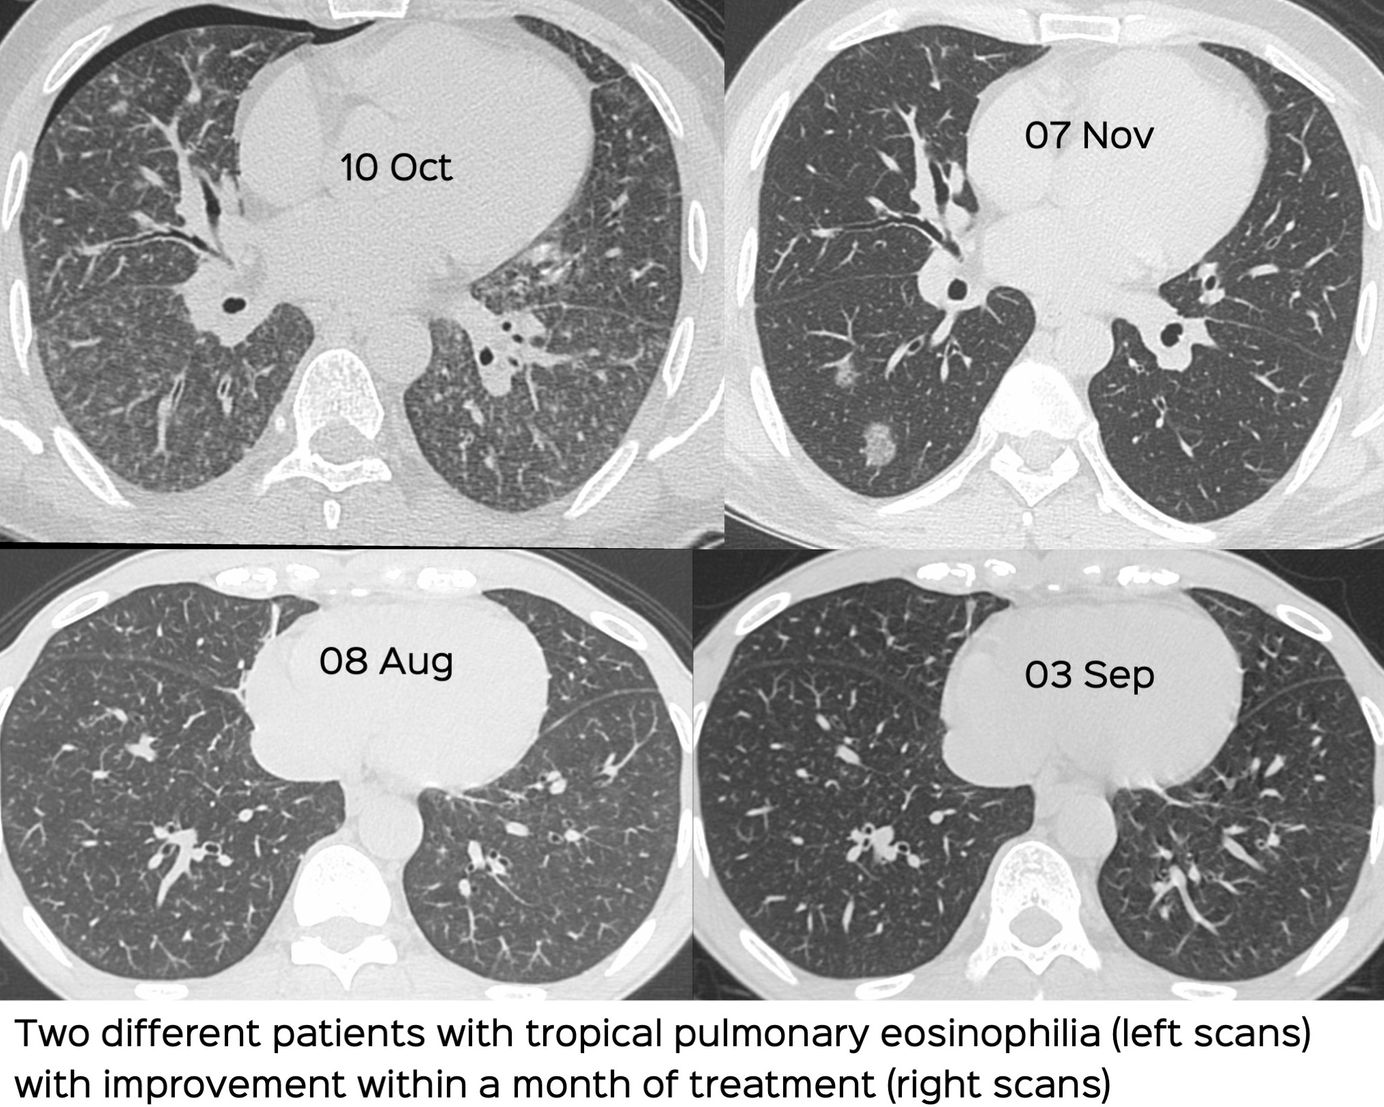

Tropical Pulmonary Eosinophilia

Unsharp, ill-defined nodules of varying sizes with ground glass halos define this condition

How to suspect tropical pulmonary eosinophilia in acute/subacute settings with diffuse lung disease, especially ill-defined bronchocentric nodules.